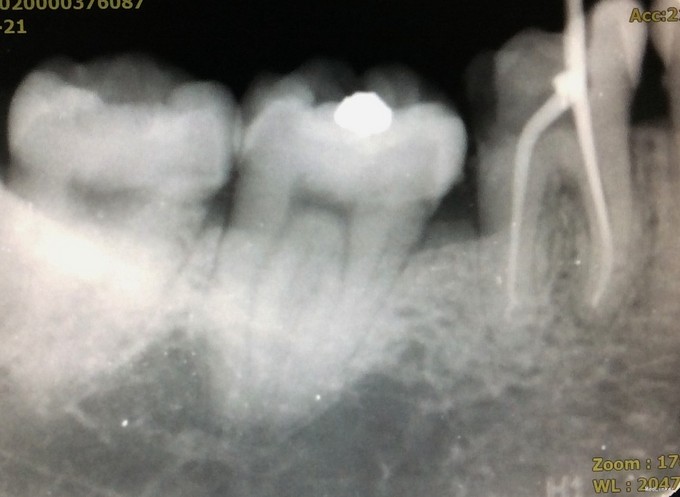

检查:46牙合面见大面积树脂充填物,部分树脂材料脱落,远中可探及继发龋,深,可探及穿髓孔,冷刺激迟钝,热刺激迟钝,电活力测试58,探(+),叩(-);牙龈及牙槽粘膜未见窦道,根尖区扪诊无不适。 X线检查:牙体组织见大面积高密度影,远中影像密度减低,累及髓腔;根尖周未见低密度影;远中牙槽嵴顶高度降低。

诊断:46牙慢性牙髓炎 治疗:46牙根管治疗+充填修复+桩冠修复 治疗经过: 首诊:去除原树脂充填物,去净龋坏,开髓,止血,封“三聚甲醛”。 首次复诊:46牙上橡皮障,揭全随室顶,显微镜下探查根管口,3根管牙,清理髓腔,#08,#10,#15不锈钢K锉疏通根管,根测仪测量根管长度,近颊根19mm,近舌根18.5mm,远中根20mm;EDTA润滑剂作用下,机用镍钛器械Protaper清扩至#2506锥度,远中根#3004,K锉疏通至#40;示尖到位;超声荡洗,次氯酸钠冲洗,干燥,根管内封氢氧化钙,髓腔置干棉球,CAVITON暂封。 二次复诊:46牙上橡皮障,去暂封,荡洗根管,次氯酸钠冲洗,干燥根管,AH糊剂加大椎度牙胶充填根尖段根管,热牙胶封闭上段根管;远中根预备纤维桩道,粘接纤维桩,行牙体树脂粘接修复。建议观察1周,若无明显不适,至修复可行冠修复。建议牙周科会诊46牙。

讨论: 1、下颌第一磨牙3根管最常见,上图清晰展示了开髓后根管口的分布。寻找根管口应注意寻找是否有远舌根,因为远舌根通常位置靠近远中边缘,若随室顶没揭全,易遗留。 2、根管预备应注意根尖孔大小。下颌磨牙通常远中根根尖孔较近中根根尖孔直径更大,行预备时应注意用K锉试探根尖孔预备是否恰当。 3、AH糊剂调拌的状态可能会影响根充的质量。本病例中,近中根、远中根均有不均匀高密度影,为相对较稠的AH糊剂。根充时应注意AH糊剂是否已固化,且应在根管中上下提拉主牙胶尖数次以使糊剂充分到达根尖处,且均匀分布于根管内。 4、若远中根根管粗大,可充填副尖以更好地封闭根尖段。 5、从该病例中可发现,远中根根尖孔开口应位于远中,不在根尖。因根尖孔的解剖位置差异大,根管治疗应充分利用根测仪测量准确的长度,不能仅凭X线片来判断。